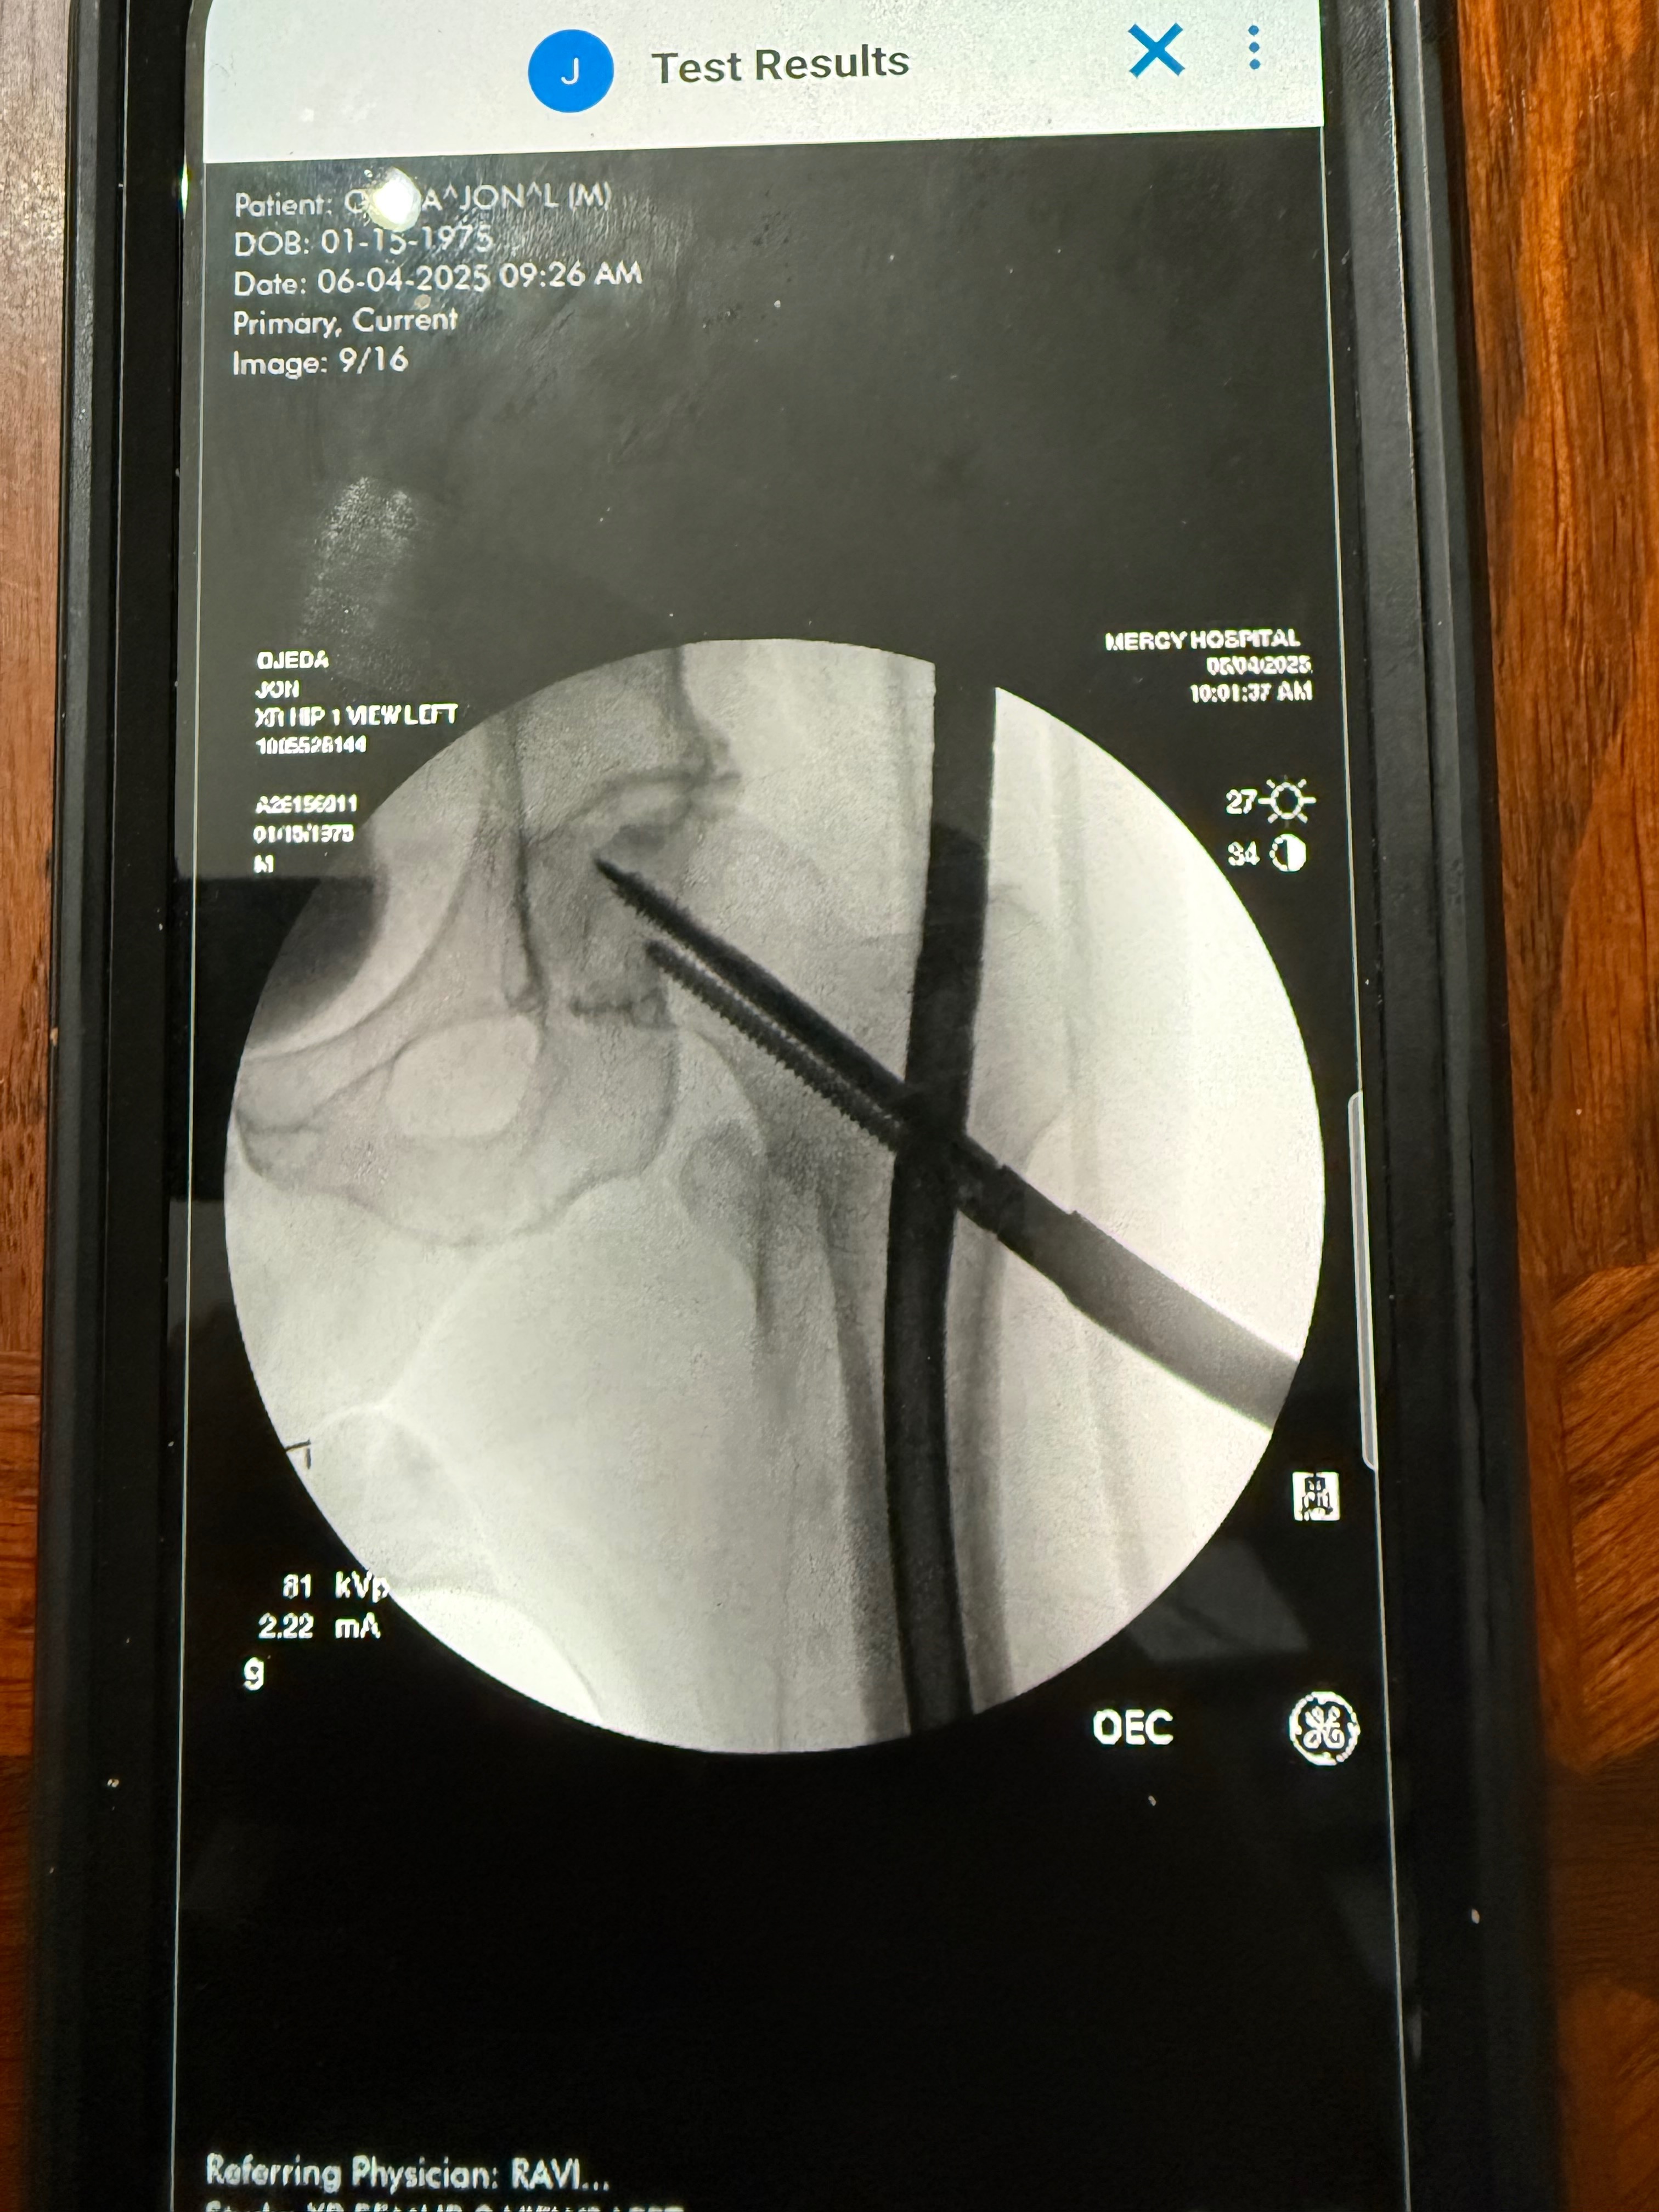

On 6/4/25, Jon was brought into surgery to have a rod (or two), two bands, and six screws placed in his thigh to hold the rods in place. He was released from the hospital on 6/5/25 with pain medication and instructions to remain at home, rest, continue follow-up appointments, and start therapy in a couple of weeks.

staples out today and more x-rays done. The rod goes directly into his femur. As of right now, he’ll be out of work at minimum another 5 weeks. Then another recheck with the surgeon. Physical therapy starting next week